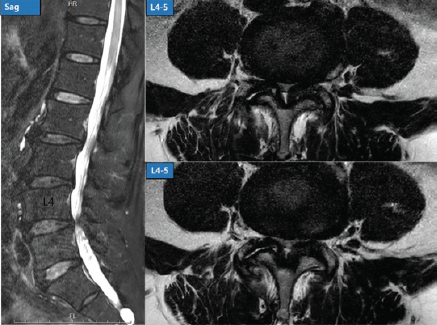

Postoperative Contralateral Facet Cyst after Endoscopic Unilateral Laminectomy for Bilateral Decompression: A Case Report

WeonMin Cho , Jae Won Shin Si Young Park , Hak Sun Kim , Seong Hwan Moon

………………………………p.52-55